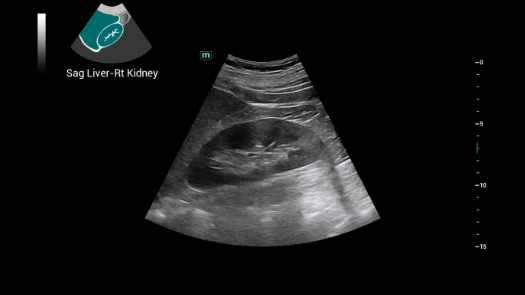

Bez wzgl?du na to, czy pracujesz w szpitalu, przychodni, czy u?ywasz ultrasonografu do badaÅ ogÃģlnych, w opiece zdrowotnej kobiet lub w badaniach sercowo-naczyniowych, w serii Consona znajdziesz bardzo pot??ne narz?dzia, aby utrzyma? si? w czo?Ãģwce.

Galeria obrazÃģw